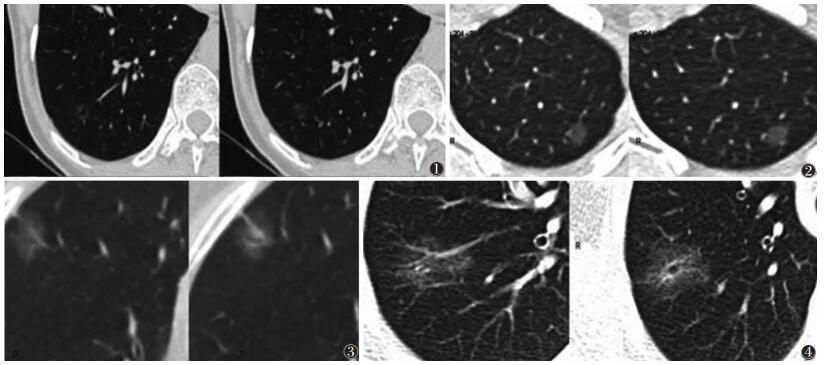

2.2 MSCT征象统计分析(表 1,图 1~4)![]() |

| 图 1 男,37岁,非典型腺瘤样增生,病灶直径约0.5 cm,CT值约-821 HU,位于右肺下叶,类圆形,瘤肺界面略毛糙 图 2 男,56岁,原位癌,病灶直径0.7 cm,CT值-697 HU,位于左肺上叶,类圆形,瘤肺界面毛糙 图 3 女,77岁,微浸润腺癌,病灶直径1.2 cm,CT值-555 HU,位于右肺上叶,类圆形,瘤肺界面毛糙,有胸膜凹陷,毛刺,浅分叶,少许实性成分 图 4 男,60岁,浸润性腺癌,病灶直径1.4 cm,CT值-597 HU,位于右肺上叶,类圆形,瘤肺界面毛糙,有分叶,毛刺,空泡,少量实性成分,邻近胸膜略凹陷 |